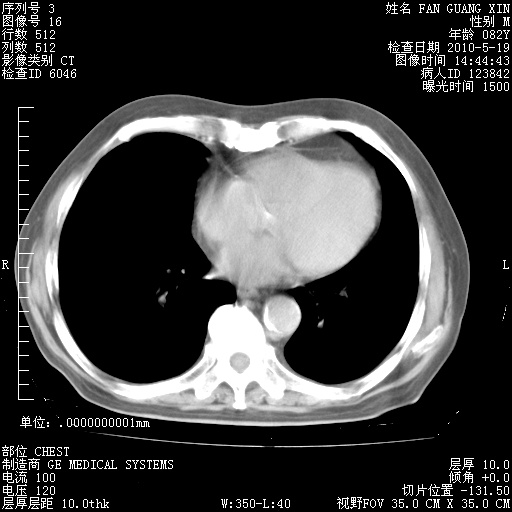

复查肺部CT,明显好转。为什么发热呢?

治疗3周后的肺部CT

治疗3周后的肺部CT纵隔窗